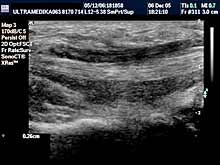

Pregledi mekih tkiva i zglobova

Pod mekim tkivima se podrazumeva potkožno masno tkivo, mišići celog

tela, dostupni nervi i regionalne limfne žlezde, a od zglobova se

prvenstveno misli na: rame, lakat, šaku, koleno i skočni zglob. |

Primenjene tehnike:

- 2D Broad band,

- Sono CT ,

- XRes,

- 3D Sono CT,

- Broad band - CD,

- CPD,

- 3D CPD panorama mod.